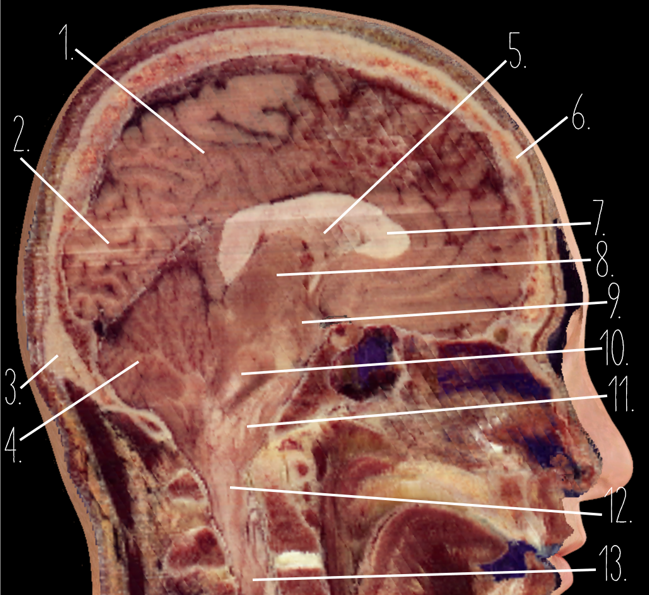

Brain Cross Sectional

127 Terms

1

Frontal Bone

2

Frontal Lobe

3?

Falx Cerebri

4?

Gray Matter

5?

White Matter

6?

Sulcus

7?

Gyrus

8?

Fissure

1?

Parietal Lobe

2?

Cerebellum

3?

Occipital Bone

4?

Cerebellum

5?

Lateral Ventricle

6?

Frontal Bone

7?

Corpus Callosum

8?

Thalamus

9?

Hypothalamus

10?

Midbrain

11?

Pons

12?

Medulla Oblongata

13?

Spinal Cord